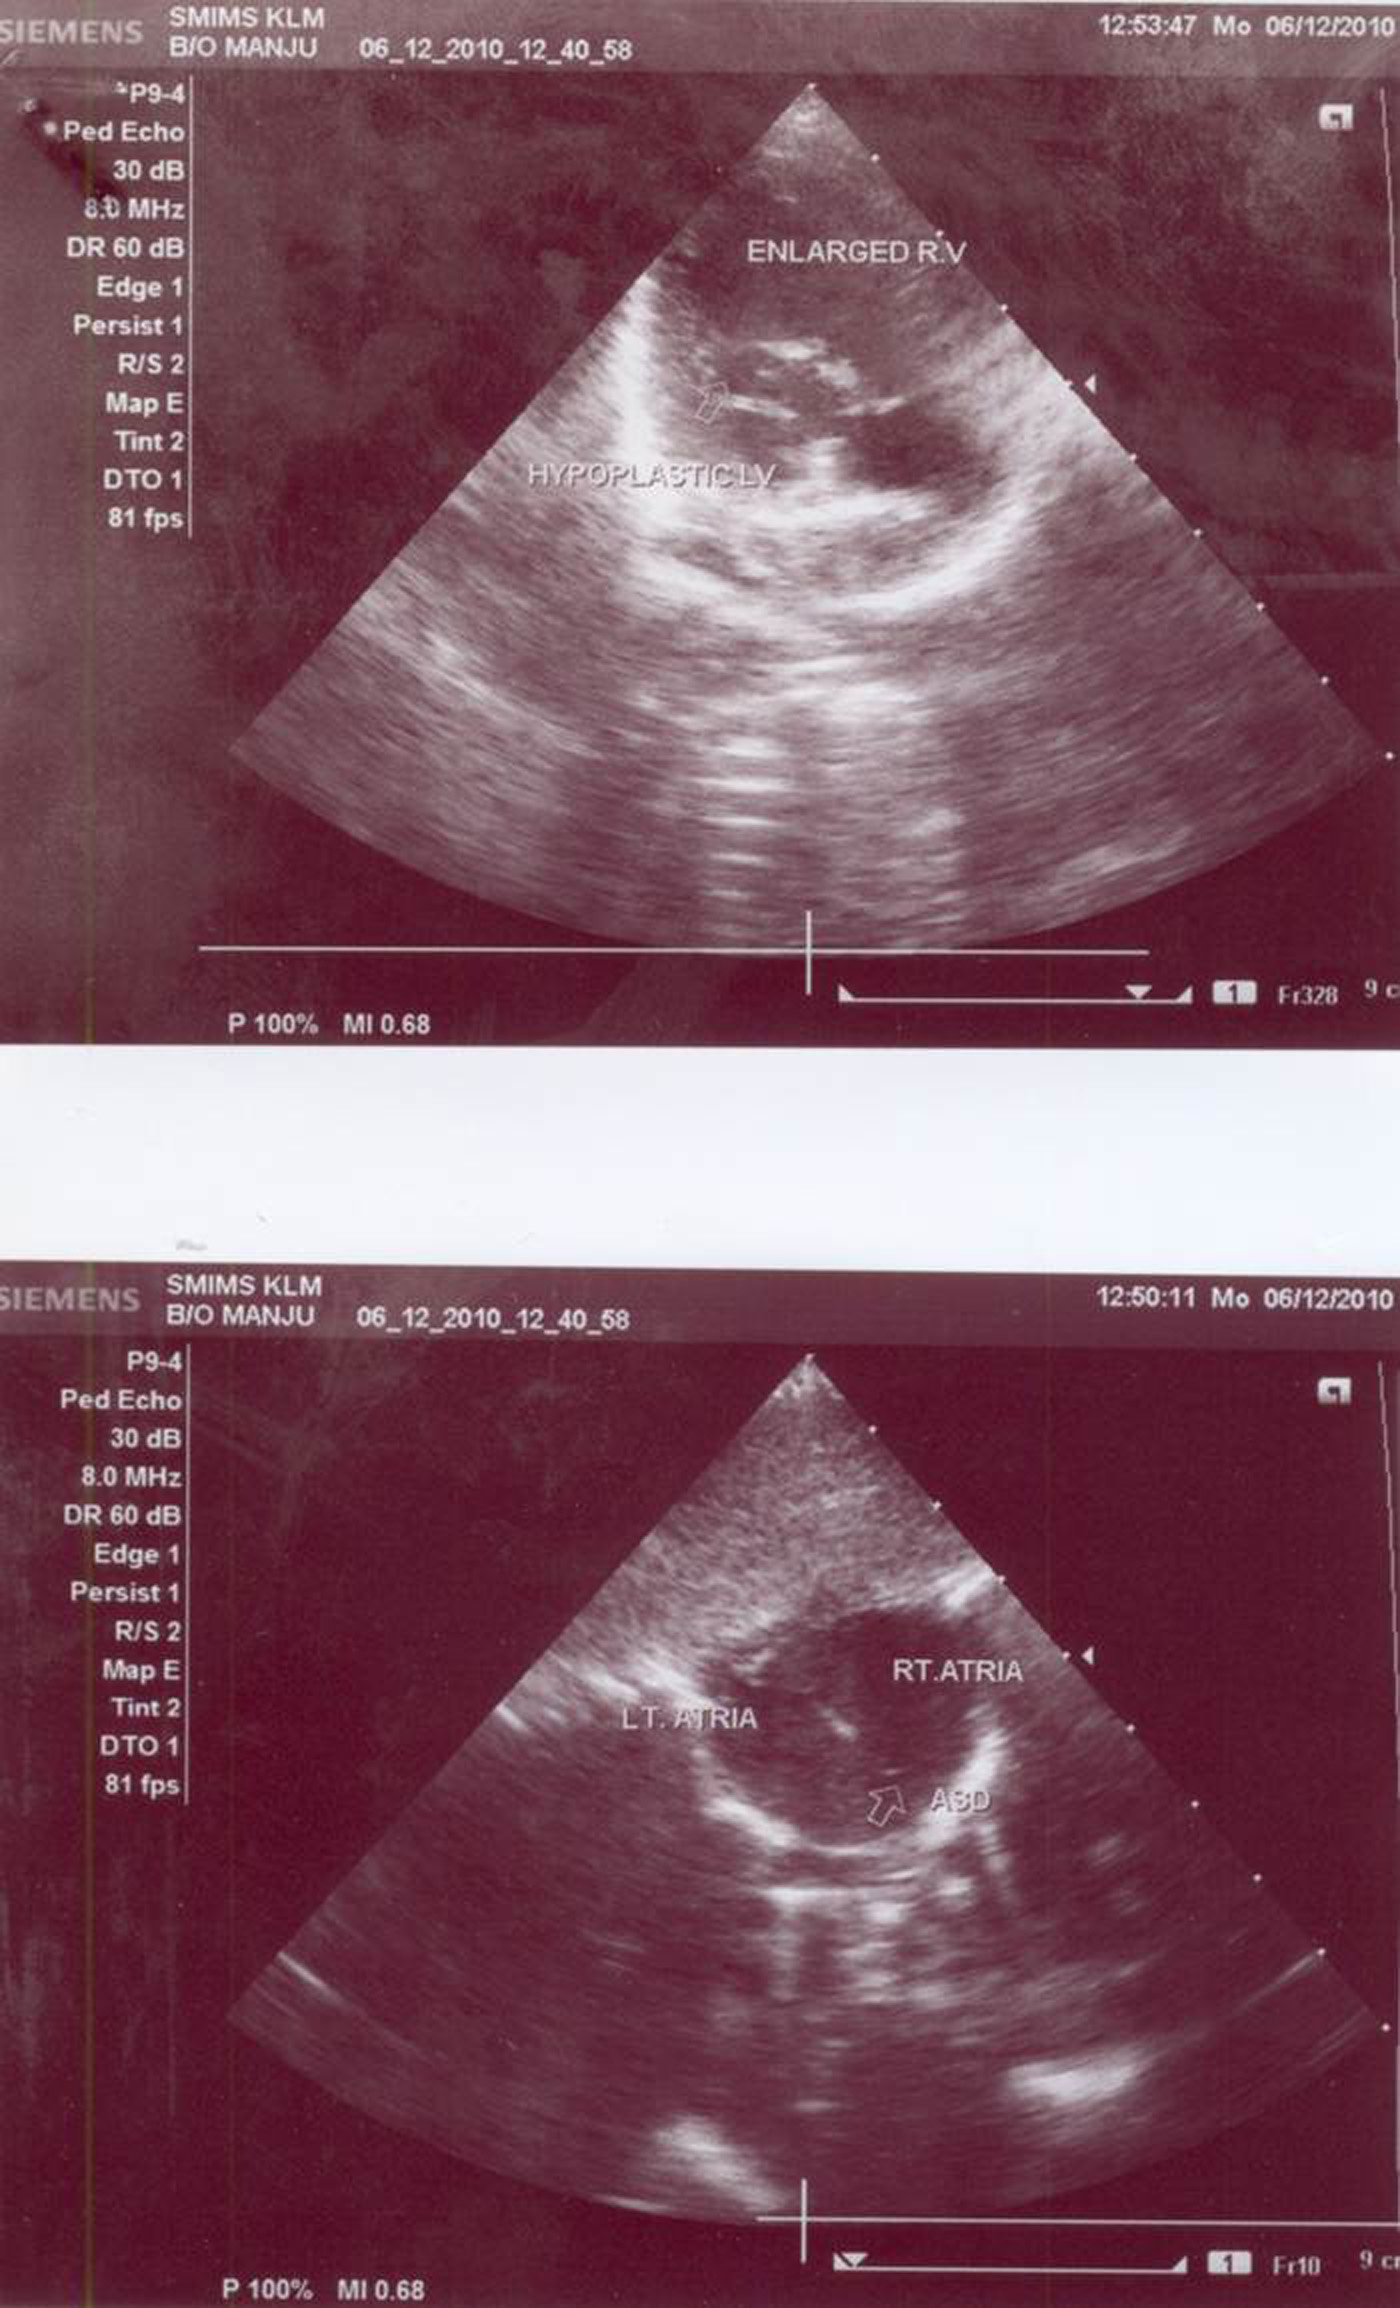

We report a case of multiple congenital anomalies in a female newborn infant, born to themother from a hill tribe. The Doppler echocardiography of the baby showed large atrial septaldefect amounting to single atrium, atretic left atrioventricular valve, large single right sidedventricle, aorta shifted to the left arising from single ventricle and diminutive hypoplasticleft ventricle. Right atrioventricular valve was normal forming single inlet into the ventricle.Pulmonary artery was small and hypoplastic and no antegrade fl ow was observed in it. Thepatient was diagnosed as having single ventricle, pulmonary atresia, patent ductus arteriosus(PDA) and major aortopulmonary collateral artery (MAPCA).